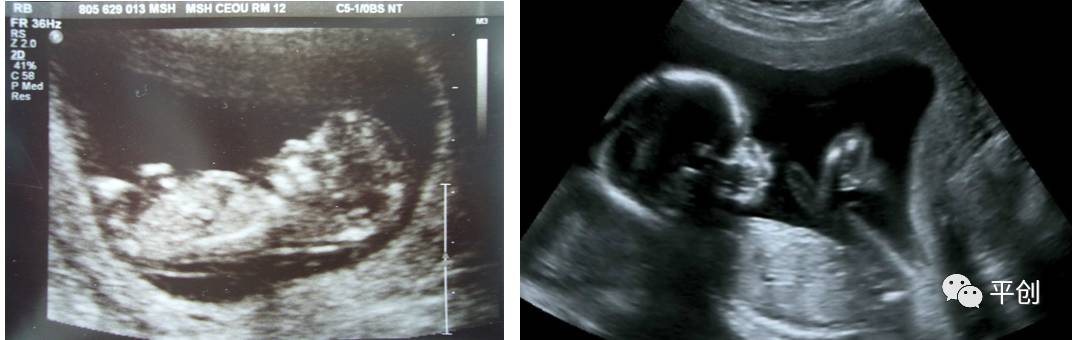

更準(zhǔn)確的醫(yī)學(xué)診斷,來(lái)自B超檢查結(jié)果的輔助,準(zhǔn)確的B超檢查結(jié)果,來(lái)自B超醫(yī)生看到的B超圖像,清晰的B超成像,來(lái)自好的耦合劑。所以說(shuō),好的耦合劑對(duì)B超的成像很重要。

而影響B(tài)超檢查成像的因素有兩點(diǎn),一是來(lái)自好的探頭,二是來(lái)自優(yōu)質(zhì)的耦合劑。如果這兩個(gè)產(chǎn)品其中有一個(gè)質(zhì)量不過(guò)關(guān),即對(duì)B超成像有一定程度的影響,可能會(huì)有成像不清楚,醫(yī)生無(wú)法準(zhǔn)確判斷所檢查器官的實(shí)際病變,嚴(yán)重的有可能度至醫(yī)生誤診的后果。

所生產(chǎn)出來(lái)的耦合劑無(wú)雜質(zhì)、透明度高、不易干,不化水,易偶合、易擦凈,透聲性超過(guò)國(guó)家標(biāo)準(zhǔn)的50%(數(shù)據(jù)通過(guò)國(guó)家指定的第三方檢測(cè)機(jī)構(gòu)檢測(cè)結(jié)果所得),完全地解決了成像不清晰的難題。

安創(chuàng)安必潔耦合劑已經(jīng)在廣東省人民醫(yī)院、南方醫(yī)院、中山大學(xué)附屬第一醫(yī)院等全國(guó)各三甲醫(yī)院使用,并得到了各醫(yī)院的一致認(rèn)可,解決了其它品牌耦合劑的偶合性差、透聲功能低,成像不清晰的問(wèn)題,減少了B超結(jié)果誤診的機(jī)率,同時(shí)也解決了短期內(nèi)要多次尋找耦合劑品牌的煩惱,所以得到了各合作醫(yī)院的聯(lián)合推薦使用:“好的耦合劑,選用安創(chuàng)安必潔消毒耦合劑。